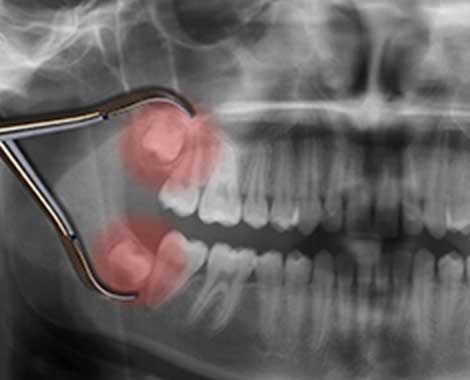

現代の人類は、顎の骨が小さくなった影響で、親知らずが生えてくるスペースが不足しがちになっています。そのため、他の歯と異なりまっすぐに生えてくることが少なく、多くは斜めに倒れて生えてきたり、まっすぐ生えてきても後ろ半分が歯ぐきで覆われたままになっていたりします。全く生えてこず、骨に埋まったままということも珍しくありません。

このようにきちんと生えてこない上に、最も奥にあるということで、歯磨きが非常に難しくなります。その結果、むし歯になりやすくなったり、化膿して腫れたりしやすくなります。

親知らずが化膿して腫れてきた場合は、その解剖学的な条件から顔まで腫れてくることも稀ではありません。それだけでなく、口を開けるのが困難になる、食べる時に喉が痛くて飲み込みにくくなるなど、食事自体が困難になるケースもあります。